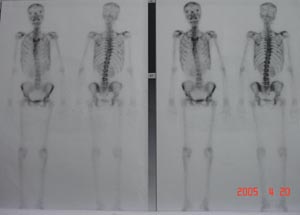

Nuclear Scan

Whole body skeletal scinti-images were obtained in anterior & posterior views after IV injection of 20 mci of 99mTc-MDP Irregular but mildly enhanced uptake is noted in both sided ribs: Both kidneys are visualiased.